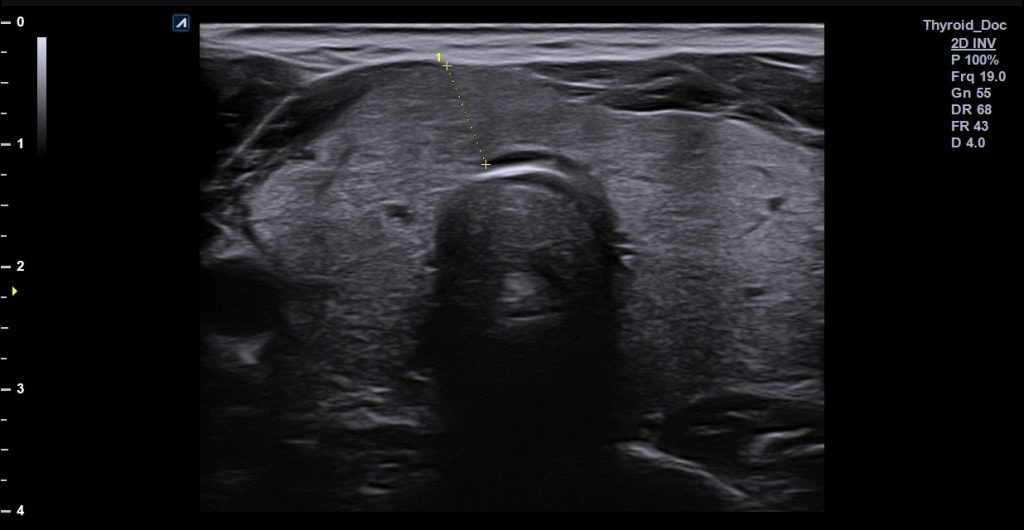

- Θυρεοειδής αδένας: Η υπερηχογραφία χρησιμοποιείται για την ανίχνευση και αξιολόγηση οζιδίων στον θυρεοειδή αδένα. Η υπερηχογραφία βοηθά να γίνει η διάκριση μεταξύ καλοήθων και ύποπτων για κακοήθεια οζιδίων. Επιπλέον, παρακολουθείτε η εξέλιξη τόσο των οζιδίων όσο και άλλων παθήσεων του θυρεοειδή, όπως η θυρεοειδίτιδα. Ήσσονος σημασίας είναι η αξιολόγηση της δομής του αδένα σε περιπτώσεις υπερλειτουργίας (υπερθυρεοειδισμός) ή υπολειτουργίας (υποθυρεοειδισμός). Τέλος ο υπέρηχος προσφέρει τη δυνατότητα καθοδηγούμενης βιοψίας και άλλων παρεμβάσεων όπως παρακέντηση με λεπτή βελόνα για τη λήψη κυτταρολογικού υλικού από τα ύποπτα οζίδια.